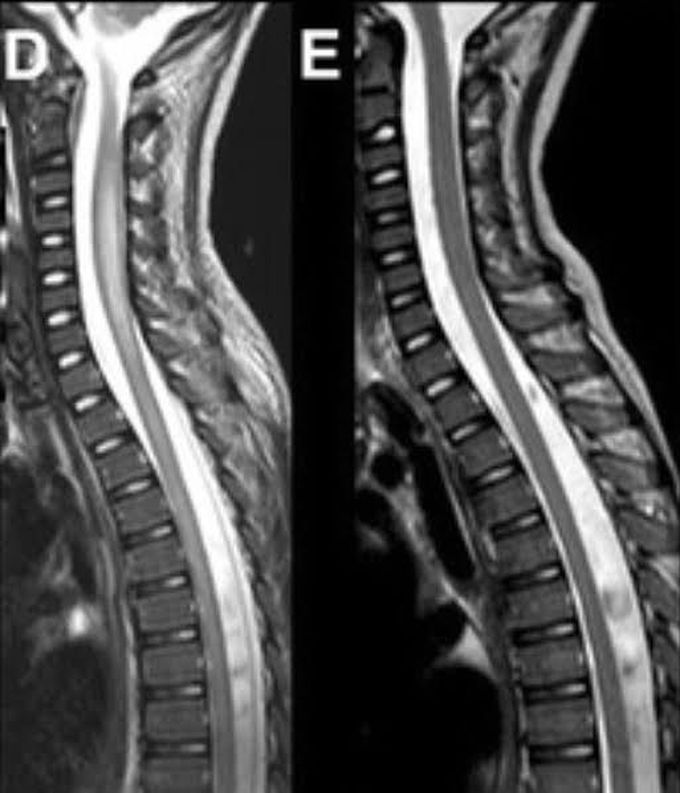

Acute flaccid myelitis

Acute flaccid myelitis (AFM) is a rare but serious condition that affects the spinal cord. It can cause sudden weakness in the arms or legs, loss of muscle tone, and loss of reflexes. The condition mainly affects young children. Most children have a mild respiratory illness or fever caused by a viral infection about one to four weeks before developing symptoms of acute flaccid myelitis.